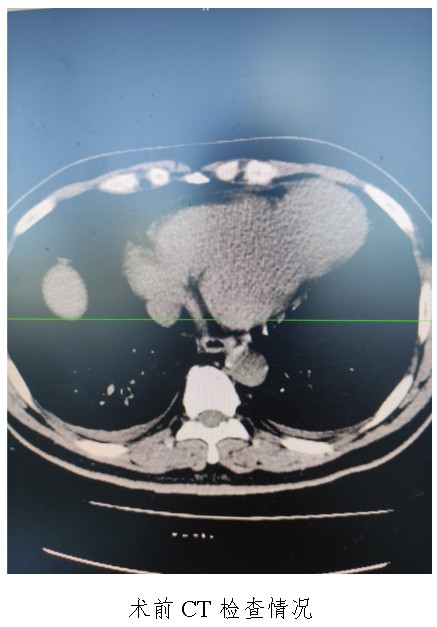

10月18日,50歲的孟先生因反復胸悶氣促一周,夜間不能平臥來衡陽市中心醫(yī)院心胸外科就診,經(jīng)心臟超聲檢查提示左心室前壁中下段及心尖部巨大室壁瘤,66×57mm,最薄處約3mm?;颊哂卸嗄晏悄虿〔∈罚韧袩o癥狀心肌梗死病史,曾行PCI治療。入科后,廖金文主任、屈云劍副主任組織心內(nèi)、麻醉、體外循環(huán)、重癥醫(yī)學科對病人病情進行了多學科討論,一致認為手術是治療該病例的唯一手段。經(jīng)過充分的術前準備,10月24日,心臟外科團隊給患者實施了左心室室壁瘤切除加左心室修補成型手術,手術順利,術后經(jīng)過精心的治療管理,患者恢復良好,康復出院。該病例的手術成功,不僅是術中及手術團隊智慧的結晶,也是多學科合作的結果,展示了衡陽市中心醫(yī)院處理復雜危重患者的能力。